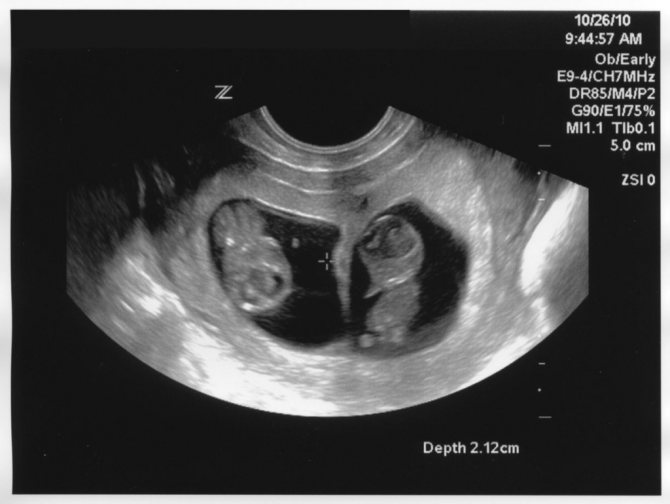

Как выглядит двойня на ранних сроках? Поначалу врач видит только два темных пятнышка. Кроме того, отчетливо прослушивается биение двух сердец, видны две плаценты и два амниотических пузыря. На фото можно увидеть снимок УЗИ близнецов.

На ранних сроках при проведении УЗИ оцениваются следующие параметры плода:

- копчико-теменной размер — КТР, близнецы обычно имеют меньшие размеры, чем одиночные эмбрионы, и к 12 неделе достигают роста 6 см и массы тела 8 г;

- бипариетальный размер — БПР, расстояние между височными костями черепа;

- частота сердечных сокращений — 110-150 уд/мин;

Нередко на снимке УЗИ заметно, что один эмбрион меньше другого. Если расхождение невелико и составляет всего лишь несколько миллиметров, то беспокоиться не нужно, размеры выровняются или в процессе беременности, или после рождения малышей.

Ультразвук

Наиболее надежный метод выявления многоплодной беременности – ультразвуковое обследование. Но его проведение на ранних сроках может показать только одного ребенка. В первом триместе вероятность выявления развития многоплодности достигает 29%, во втором и третьем -96%. Иногда происходят невероятные случаи обнаружения при родоразрешении третьего ребенка, не зафиксированного при скринингах.